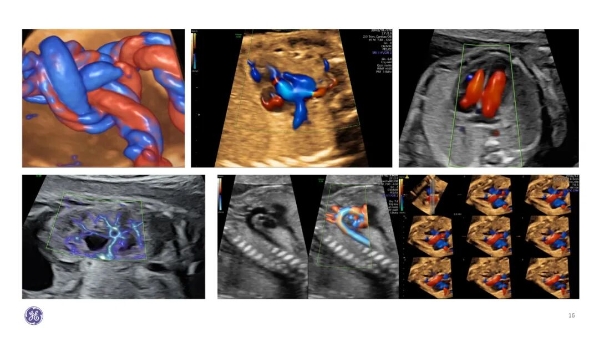

什么是胎儿心脏超声?

通过胎儿心脏超声检查,一方面,可早期识别那些复杂、严重的先心病,减少对家庭和社会造成的不利影响,实现优生优育;另一方面,可以早期诊断可矫治的先心病,有利于及时干预和合理咨询,让患病宝宝早诊断、早治疗。这两种超声一起形成了母婴双筛查策略。